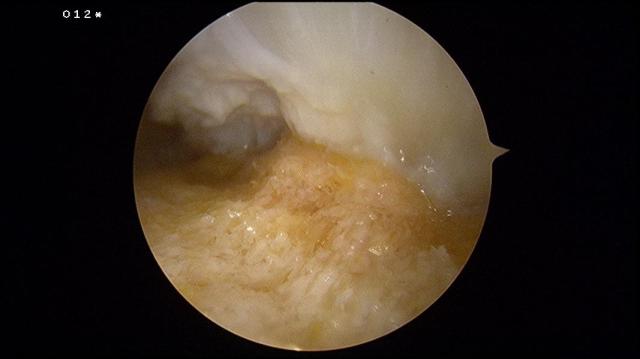

resector is placed and visualized by the arthroscope. The inflamed retrocalcaneal bursa is removed to provide a better view.

The superior surface of the calcaneus is visualized, and its fibrous layer and periosteum is stripped off using a radiofrequency wand.

The Haglund’s exostosis is exposed.

When the foot is brought into full dorsiflexion, the impingement site is determined.

A 4.0mm hooded arthroscopic burr is used to remove the Haglund’s exostosis. All of the time the opening of the burr is facing the bone. The foot is placed in full plantarflexion and the posterior superior bone rim can be removed.

Upon completion of the procedure, the exostosis should be flattened and the insertion of the Achilles tendon into the heel bone should be clearly seen.